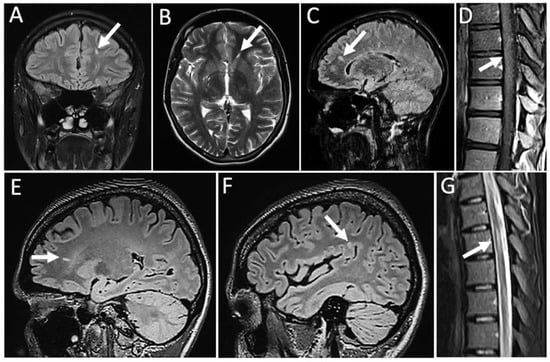

2. Case Report

3. Results